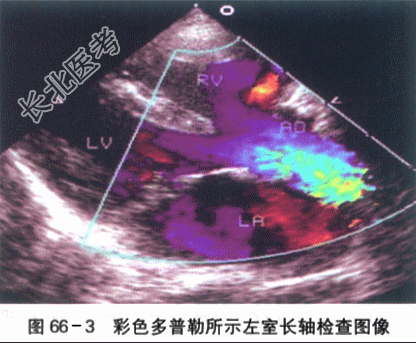

患儿,男,2岁3个月,因"哭吵后口唇发绀伴气促1h"就诊。患儿入院前1h剧烈哭吵后出现口唇发绀、呼吸急促、家属安抚后无明显改善,送入急诊。出生6月龄前患儿无特殊病史,6月龄后患儿偶有哭吵后口唇青紫,增有剧烈哭吵后呼吸快,口唇发紫加重,安抚后好转;在当地住院发现有心脏杂音,做了一些检查后诊断心脏病(具体不详)。平素活动量少,喜静不喜动,喜抱,偶尔有走路时反复下蹲。目前饭虽少,身高、体重均不及同龄儿。大小便正常。患儿为G₁P₁,孕39周自然分娩。BW3200g。否认孕期感染或服药史,否认围产期窒息缺氧病史。否认家族心脏病或其他遗传病史。体格检查:T37℃,P148次/min,R52次/min,BP78mnlHg/40mmHg,Wt10.1kg,Ht78cm,SaO₂68%。烦躁,全身大汗,口唇发绀,可见杵状指,四肢脉搏稍弱,对称。肺部检查两肺呼吸音粗稍粗,未及明显啰音。心前区饱满,心尖搏动位于第4肋间左乳线上,范围约2cm;HR118次/min,规则,2~3LSB SMⅠ~Ⅱ级,粗糙,P2略增强,无分裂。腹部平软,肝脏肋下2.5cm,质地软。脾未触及。双下肢无水肿。实验室检查(1)心电图检查:窦性节律,右房、右室增大。电轴右偏,Ⅱ导联P波高尖,呈双峰,时限=0.12s。V₁导联QRS波群呈R形,V₅导联QRS波群呈RS形;ST段压低,V₃~V₅导联T波倒置。如图66-1所示。(2)X线胸片检查:右房、右室大。心胸比例0.65,心影呈"靴型"心,心尖圆钝、上翘;肺动脉端内凹,肺血少。如图66-2所示。(3)超声心动图检查:心脏位置及连接正常。右房、右室增大,右室壁肥厚,左室收缩活动正常。主动脉增宽,骑跨于室间隔上50%。左右冠状动脉开口可见,肺动脉瓣及瓣下狭窄,瓣环0.67cm,总干内径1.29cm,流速2.3m/s,右室流出道狭窄肌肉肥厚,过此处血流少,流速约2.8m/s。左肺动脉开口0.82cm,内径0.97cm;右肺动脉开口10.78cm,内径0.85cm。房室瓣开放活动可。房间隔完整。室间隔缺损,对位不良型,双向分流。左位主动脉弓。如图66-3所示。